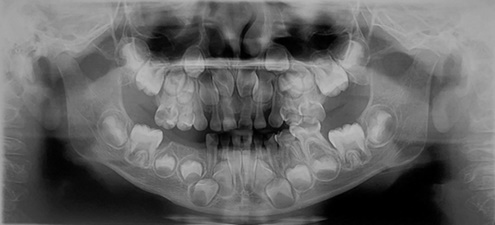

Paciente masculino de 5,4 años se presenta a Clínica de Odontopediatría y Ortodoncia de la Universidad de Ixtlahuaca CUI, acompañado de su tutora quien niega antecedentes heredofamiliares. Al interrogatorio indirecto refieren que 6 meses atrás presentó proceso infeccioso de lado inferior derecho relacionado a molares, fue intervenido de forma intrahospitalaria en donde se realizó abordaje quirúrgico para el manejo y control del proceso infeccioso, resultando en la extracción del primer y segundo molar primario inferior derecho (Figura 1).

Figura 1 Radiografía Panoramica Inicial. Se observa ausencia de molares primarios inferior derecho asi como el primer molar primario en estadio 7 de Carmen Nolla.

Con respecto al caso presentado, la corona del primer molar primario ya se encontraba totalmente formada y con ruptura de la cripta alveolar, como se observa en la imagen 1, el inicio de la erupción activa del primer molar iba comenzando, por lo que el abordaje con la zapatilla distal fue el correcto para evitar continuar con una mesialización para buscar su guía eruptiva.